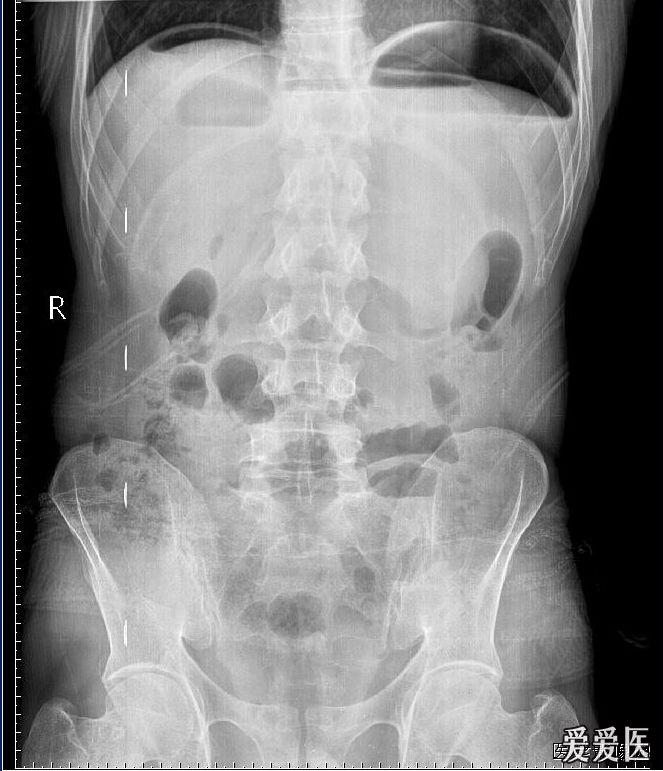

消化道穿孔,膈下间隙积液.jpg